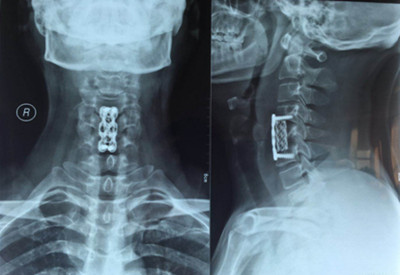

图片二:

因患者年龄较轻,双下肢无力症状明显,病变区脊髓信号改变,保守治疗病情会继续发展,后期脊髓神经变性,压迫症状加重,严重影响肢体功能,必须尽早手术。骨一科主任杨志奎带领曹熙、田涛、张凯迪医师为其实施了颈椎前路颈5椎体次全切、椎管减压植骨融合内固定术。手术历时3小时顺利完成。术后第二天,患者双手指麻木症状明显缓解,四肢关节活动均正常。第三天配带颈托保护下床活动锻炼,双下肢无力症状明显减轻。患者现已康复出院。